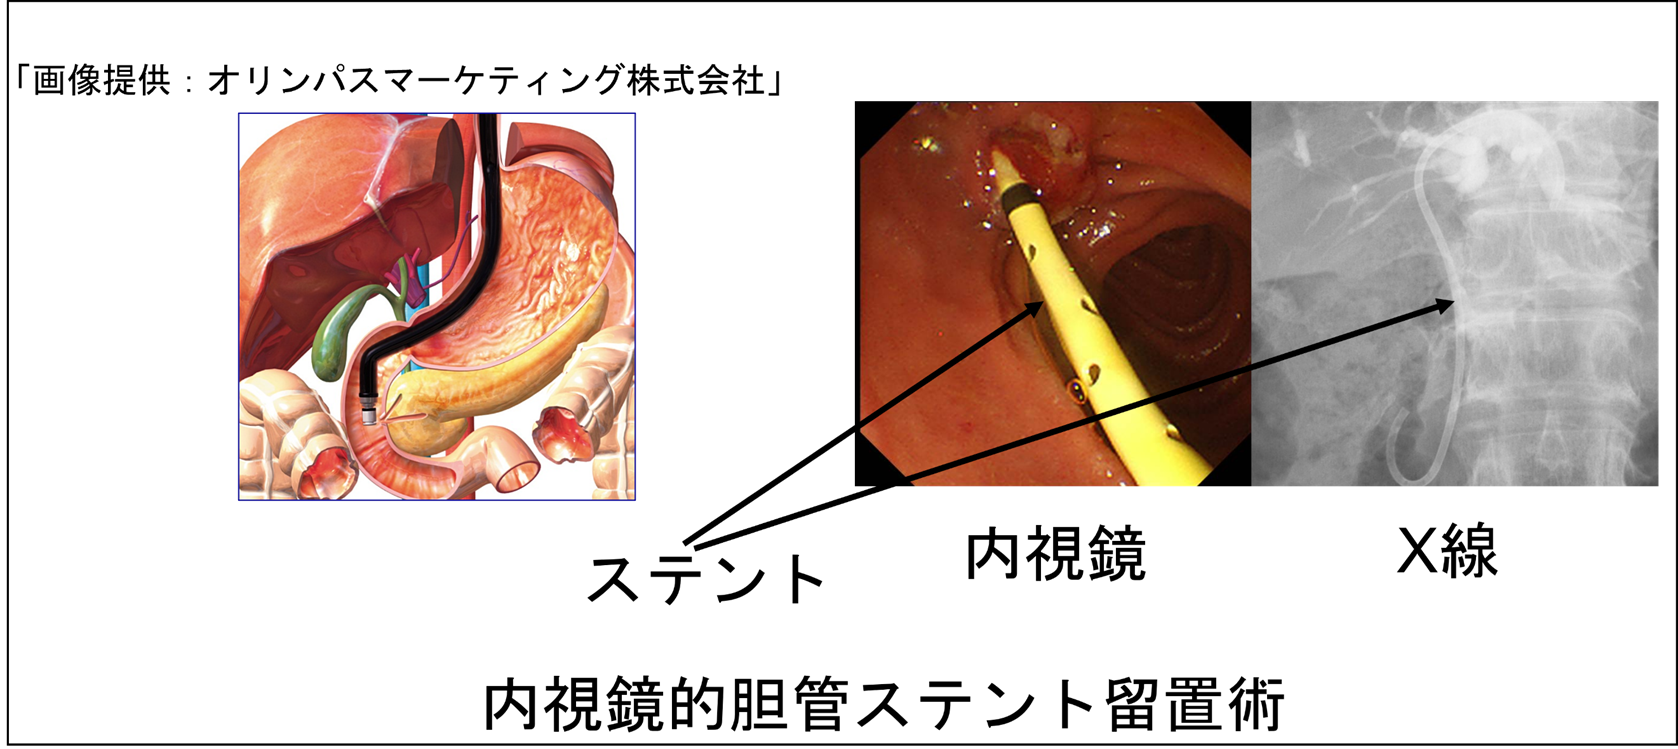

(1)内視鏡的逆行性胆管膵管造影(ERCP)

胆道(胆管・胆嚢)や膵臓に対する内視鏡での検査・治療について説明します。口から内視鏡を入れて行います。主に使うのは十二指腸鏡か、超音波機能が付いた専用スコープです。胃や小腸の手術で消化管のつなぎ方が変わっている方には、先端に小さな風船が付いた小腸用スコープを使うこともあります。通常は、点滴で鎮静剤(よく眠くなる薬)を投与してから行います。以下に具体的な手技を紹介します。